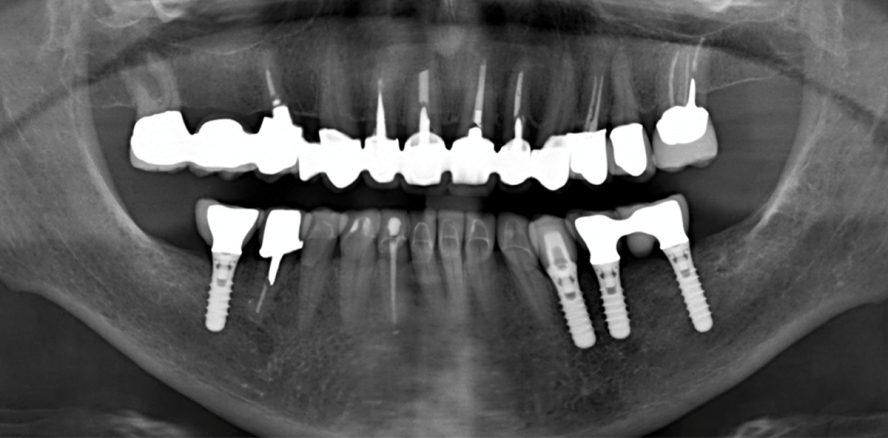

Das Orthopantomogramm aus dem Jahr 2003 (Abb. 1b) dokumentiert die dentale Situation zu diesem Zeitpunkt: Kronen- und Brücken auf z. T. endodontisch behandelten Zähnen im Oberkieferfront- und im Ober- und Unterkieferseitenzahnbereich, multiple Füllungen an den Unterkieferfrontzähnen.

Kurze Zeit später klagte die Patientin über Schmerzen bei Pfeilerzahn 38. ­Gemeinsam mit einem Kieferchirurgen wurde folgende Behandlung geplant: ­Extraktion von Zahn 38 (nach Durchtrennen der Brücke distal der Krone 34), VMKs auf Implantaten 35-36 und 46, ­gegossener Stiftaufbau und VMK bei Zahn 45. Die ­Patientin war einverstanden, wünschte vorerst keine darüber hinausgehende Sanierung. Im Rahmen der üblichen diagnostischen Abklärung und Vorbehandlung (Mundhygiene!)16 wurde klinisch und axiografisch ein intermediäres reziprokes Kiefergelenkknacken rechts festgestellt. Daher wurde auf eine gute posteriore Abstützung mit den neuen Kronen besonders geachtet. Die Abbildungen 2a und b geben die klinische Situation nach deren Einsetzen wieder. Die Patientin war beschwerdefrei und erhielt eine stabilisierende ­Zentrikschiene für die Nacht.